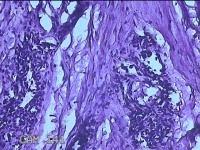

右侧手掌肉芽组织

性别

女

年龄

48岁

临床诊断

手掌开放性损伤

一般病史

右侧手掌肉芽组织增生

标本名称

大体所见

灰白暗红色带皮肤样组织1.3x0.8x0.3cm一块,切面灰白粉红色,质软。